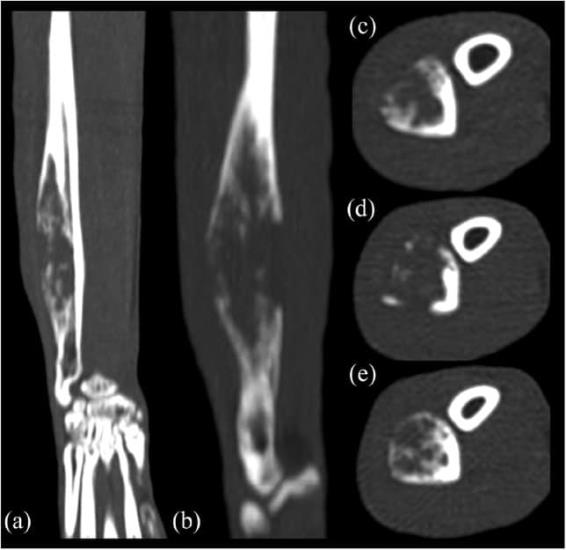

Based on the radiographic findings, our differential diagnoses were primary bone tumour, secondary bone tumour, osteomyelitis and bone cyst (eg, aneurysmal bone cyst). To better characterise the mass and rule out pulmonary metastasis, a CT scan of the forelimbs and thorax was performed. The scan was carried out under general anaesthesia using a four-slice CT scanner (GE LightSpeed; General Electric Healthcare). The patient was positioned in sternal recumbency with the forelimbs extended and parallel to each other. On the CT workstation, images were acquired with soft tissue, pulmonary and bone algorithms, and reformatted in sagittal and dorsal planes. The images were reviewed using a DICOM viewer application (Horos, version 3.3.0; GNU Lesser General Public License) using soft tissue (Window Width [WW] = 400, Window Level [WL] = 40), pulmonary (WW = 1400, WL = −500) and bone windows (WW = 1500, WL = 300). Adjustments to image window width and level were made as needed.

The CT images showed a monostotic, diaphyseal, fusiform, expansile, highly lytic mass involving the cortex of the ulna, sparing only the medial aspect and measuring 42 × 11 × 9 mm (Figure 2). There was no evidence of sequestrum formation. There was moderate ground-glass opacity and mild bronchial wall thickening affecting the right middle, right caudal, right accessory and left caudal pulmonary lobes. There were four areas of hyperdense alveolar filling observed in the right pulmonary lobes (Figure 3). These areas were fairly well defined and highly attenuating; they were localised to the dorsal and middle aspect of the right caudal lobe, ventral aspect of the right middle lobe and caudal portion of the right cranial lobe. Some of the bronchi involved in these areas of consolidation were truncated. No lymphadenomegaly was evident. Differentials for the pulmonary findings were multifocal infectious disease, haemorrhage and pulmonary metastatic disease (less likely). Atelectasis was ruled out because the areas of hyperattenuation were in a non-dependent position, and both lungs were optimally inflated and symmetrically expanded.

Figure 2 (a) Dorsal, (b) sagittal and (c–e) transverse multiplanar CT reformatted images of the right antebrachium. Cross-sectional imaging confirms the features of the ulnar lesion and better highlights the severity of the geographical lytic pattern